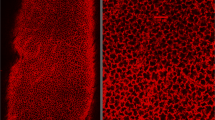

The tracheal segments had a radius of 0.33 ± 0.01 (SE) cm, a length of 2.70 ± 0.19 (SE) cm, and a resting volume of 0.96 ± 0.11 (SE) mL. Application of collapsing pressure to the relaxed tracheal segment typically caused invagination of the pars membranacea at lower collapsing pressures, whereas at higher collapsing pressures the lumen assumed an asymmetric comma or curl formation (Fig. 2). After exposure to MCh, the posterior membrane appeared more prominent but shorter in its transverse dimension under resting conditions. Additionally, when the tracheae were exposed to collapsing pressures, the lumen remained round, and the curl formation was less prominent (Fig. 2). Typical pressure-volume and pressure-area curves are shown in Figures 3 and 4. For both types of measurement, hysteresis was present between descending and ascending limbs of the curves (Fig. 3). Furthermore, the mean values of maximum collapsibility of the unstimulated airway, defined as the percent decrease from baseline in either volume or area at -4.0 kPa PTM, were similar for both methods (-70 ± 4% SE Δvolume; -72 ± 3% SEΔarea) (Figs. 3 and 5).

Bronchoscopic views of a single tracheal lumen at varying PTM before (a-d) and after (e-h) MCh administration. Numbers refer to the PTM (kPa) at which the image was taken. In the unstimulated trachea, as PTM became negative, the posterior membrane invaginated into the lumen (b, -2.0 kPa PTM). As PTM became more negative, the posterior membrane deformed asymmetrically creating a “curl” or comma formation(c, -3.0 kPa PTM and d, -4.0 kPa PTM). After MCh administration, invagination and curl formation of the posterior membrane was markedly diminished at every PTM, and the luminal area was better preserved. The decrease in cross-sectional area from baseline at -4.0 kPa PTM for the unstimulated airway was -79%, whereas after MCh administration it was -51%.

Despite the influence of fixation on the ends of the airway segments, images from middle sections of our preparation demonstrated changes in the shape of the lumen consistent with changes noted in other studies. Invagination of the pars membranacea and curling of the tracheal cartilage have been described in the relaxed trachea subjected to compressive pressures(19, 35, 36). In contrast, described in these same investigations was preservation of the tracheal lumen after stimulation of the smooth muscle, even when the airway was subjected to high collapsing pressures.